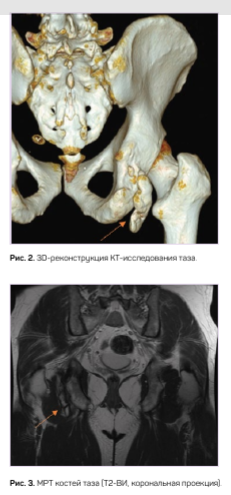

Нами было выявлено 2 случая врожденной аномалии. У пациента С. при полипозиционном рентгеновском исследовании обнаружен отдельно лежащий костный фрагмент в мягких тканях параартикулярно, имеющий фрагментарное строение. На рентгенограммах правого тазобедренного сустава при полипозиционном исследовании в области седалищного бугра определяется свободнолежащий фрагмент костной плотности, с трабекулярной структурой, с четкой замыкательной пластинкой, полигональной формы, размером 75,0 х 23,0 мм (рис. 1).